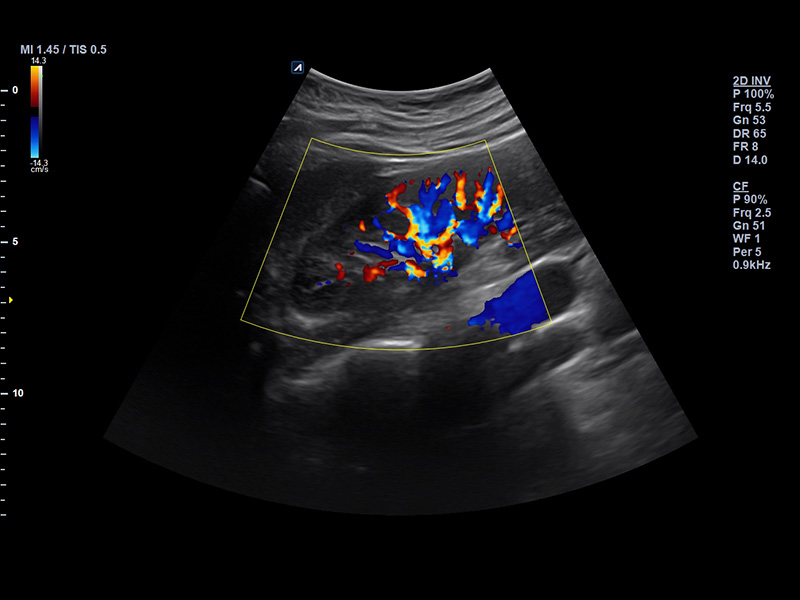

SC2-11H

X+ Crystal Signature™ Microconvex(2~11MHz)

Application:

Abdomen, Pediatric, OB/GYN, Urology, EM